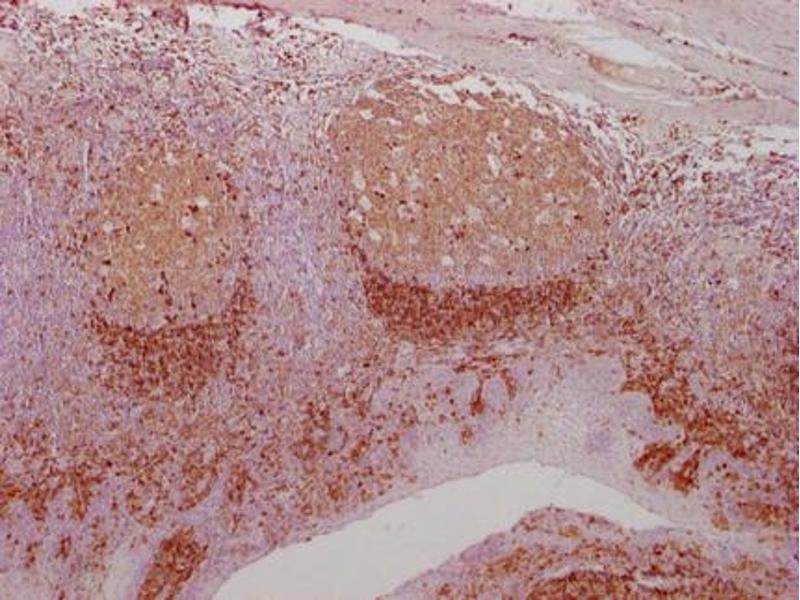

CD79a anticorps

- CD79A Monoclonal Antibody